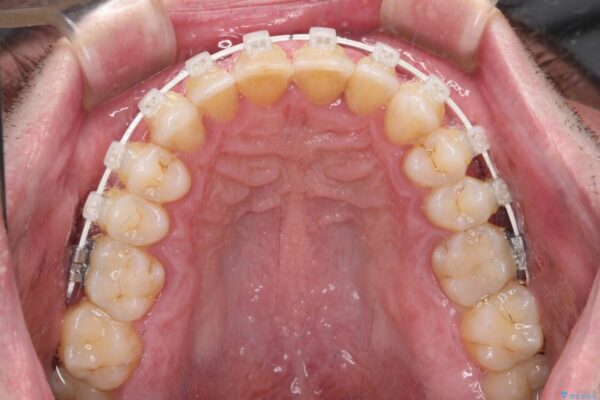

治療途中

• 前歯でものを噛みきりたい 目立たない装置でのワイヤー矯正 治療途中画像